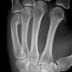

The fifth metacarpal bone (metacarpal bone of the little finger or pinky finger) is the most medial and second shortest of the metacarpal bones.

It presents on its base one facet on its superior surface, which is concavo-convex and articulates with the hamate, and one on its radial side, which articulates with the fourth metacarpal.

On its ulnar side is a prominent tubercle for the insertion of the tendon of the extensor carpi ulnaris muscle.

The dorsal surface of the body is divided by an oblique ridge, which extends from near the ulnar side of the base to the radial side of the head. The lateral part of this surface serves for the attachment of the fourth Interosseus dorsalis; the medial part is smooth, triangular, and covered by the extensor tendons of the little finger.

A fracture of the fourth and/or fifth metacarpal bones transverse neck secondary due to axial loading is known as a boxer's fracture. The fifth metacarpal bone is the most common bone to be injured when throwing a punch.